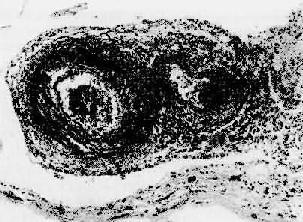

病变多呈节段性,以血管分叉处最为常见。内眼观,病灶处形成直径约2~4mm的灰白色小结节,结节之间的血管壁外观正常。镜下,急性期表现为急性坏死炎症,病变从内膜和中膜内层开始,扩展至管壁全层及外膜周围,纤维素样坏死颇为显著,伴炎细胞浸润(图4-13)尤以嗜酸性及中性粒细胞为多,继而有血栓形成。以后的进展是纤维增生,管壁呈结节性增厚,管腔机化阻塞和明显的动脉周围纤维化。值得注意的是早期炎性坏死变化及后期胶原化可同时存在。病变的主要后果是缺血性损害和梗死形成。

结节性多动脉炎

图4-13 结节性多动脉炎

两个动脉壁的各层都有炎性细胞浸润,外膜尤为显著。中膜发生纤维素样坏死